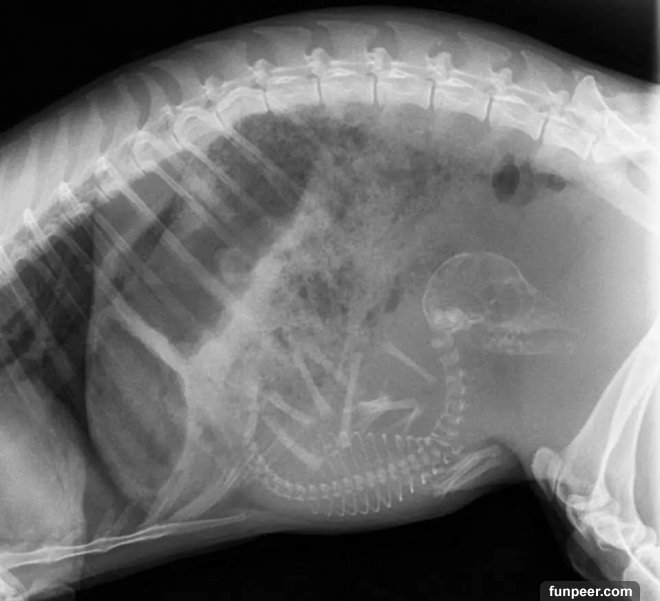

貓媽媽的X照片是這樣的

另一張貓的照片,有許多小貓

最後,又是貓,有五個生命將誕生!